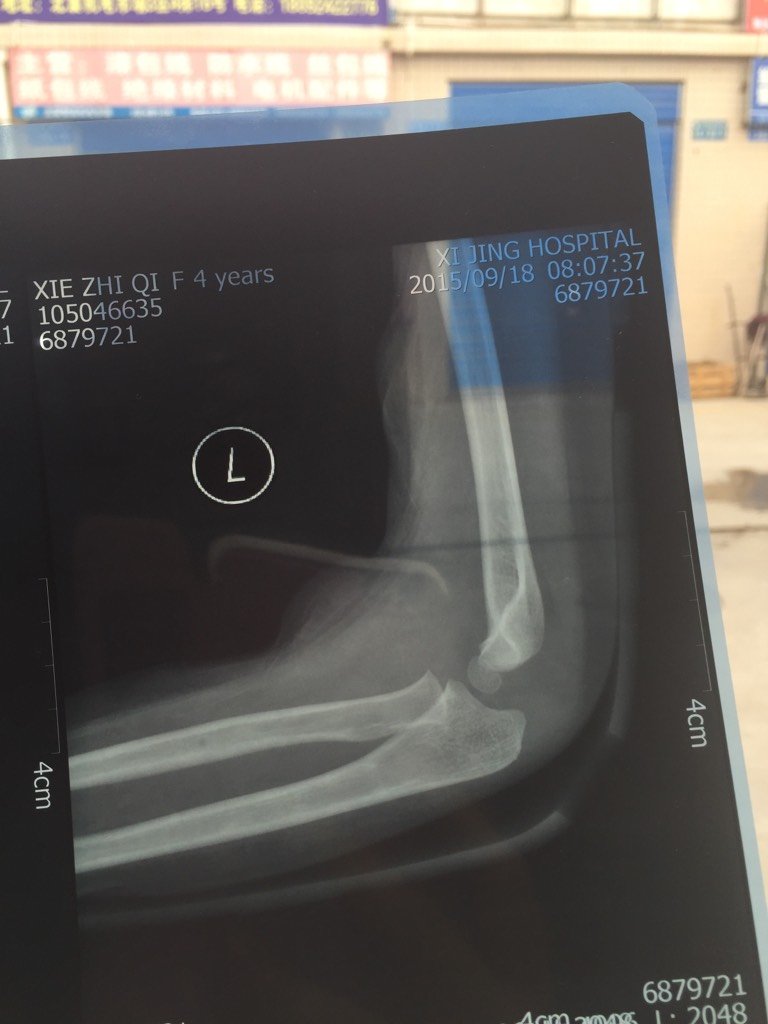

小孩肱骨外髁骨折.这是肢具固定后的照片 没固定之前没有移位 不知道这固定后什么情况 还没找医生 小孩肱骨外髁骨折..这是肢具固定后的照片.没固定之前没有移位.不知道这固定后什么情况.还没找医生.好着急.谁帮我看看. 点击展开 ″筱雅★ 2015-09-19 20:21 为您推荐: 其他回答 算是个裂缝骨折吧,没有问题 _ 2015-09-19 21:41 游离的那一块? _ 2015-09-19 21:25 看起来可以 _ 2015-09-19 20:53 你好,伤了多久了?好像照片看不到? _ 2015-09-19 20:25 相关问题 非常感谢! 在下左肱骨下段骨折,内固定,九个月了,固定有轻度移位 我要怎么办 我小孩是在校学生、寒假期间被人打 左手肱骨近端骨折轻度移位、请问能定什么伤? 三岁小孩拍片左肱骨外髁上骨折,未见移位,左肘关节未见脱位,请问严重吗?该怎样处理和照顾?谢谢